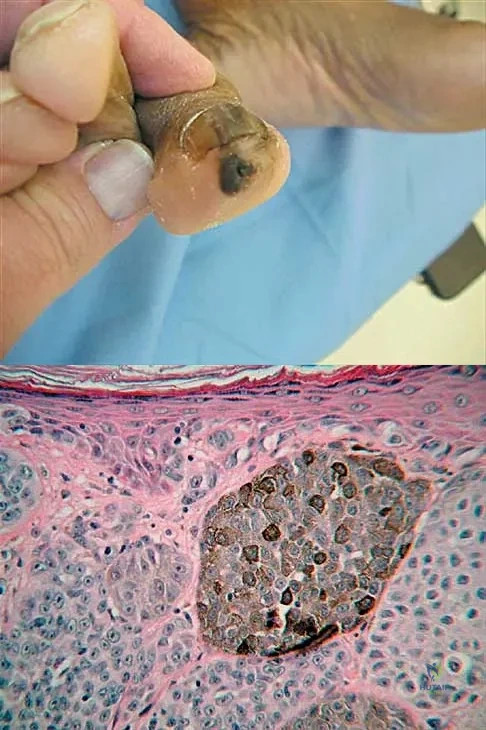

A 38-year-old woman has a lesion on her left foot that has increased in size over the past 6 months. The clinical photograph is shown in Figure 17a, and a photomicrograph of the biopsy specimen is shown in Figure 17b. What is the most likely diagnosis?

Explanation

Melanoma comprises 25% of lower extremity lesions and is the most common malignant tumor of the foot. The preferred treatment is wide resection. Hughes LE, Horgan K, Taylor BA, Laidler P: Malignant melanoma of the hand and foot: Diagnosis and management. Br J Surg 1985;72:811-815.